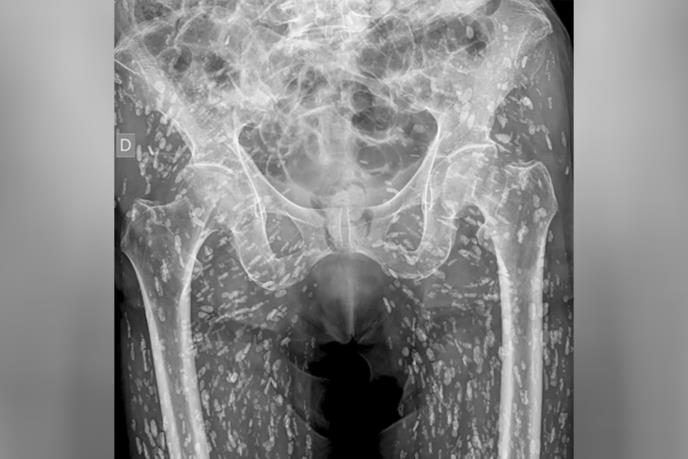

Jedan doktor hitne pomoći nedavno je podelio "jedan od najluđih rendgenskih snimaka koje je ikada video", na kojem je prikazana osoba čiji je donji deo tela bio preplavljen stotinama kalcifikovanih jaja pantljičara.

Sam Gali, doktor hitne pomoći specijalizovan za kardio-vaskularne hitne slučajeve i hitnu radiologiju, nedavno je podelio neobičan rendgenski snimak iz oblasti karlice pacijenta na kojem je njegovo telo bilo ispunjeno stotinama belih tačaka. Sve ove tačke su bila okalcifikovana jaja pantljičare koja su se zaglavila u mekim tkivima donjeg dela njegovog tela. Zanimljivo je da pacijent nikada nije znao da ima cisticerkozu i saznao je za to tek kada je došao na rendgenski pregled nakon što je pao i osetio bol u kuku.

"Ovo je stanje poznato kao cisticerkoza, zapravo ovo su larve cista taenia solium, poznate i kao svinjska pantljičara," rekao je Gali na društvenoj mreži X. "Ove ciste mogu putovati bilo gde kroz celo telo, uglavnom u mišiće i meka tkiva kukova i nogu."

Osim ako ne dospeju do mozga, ova kalcifikovana jaja su zapravo bezopasna, više nisu održiva, ali ako vam je sama pomisao na to da vas okupira stotine ovih cista sličnih zrnu pirinča nezamisliva, treba da izbegavate sirovo ili nedovoljno kuvano meso svinja i ribe, kako biste bili sigurni.